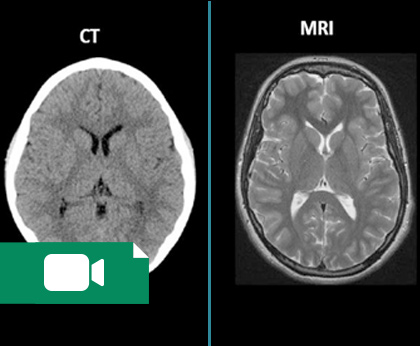

متخصصین رادیولوژی از مهارت کافی برای عکسبرداری و کار با روشهایی مانند عکسبرداری پرتوی یونیزان مانند رادیوگرافی، ماموگرافی و سیتیاسکن برخوردار است. همچنین میتواند از روشهای پرتوی غیر یونیزان مانند ام آر آی، سونوگرافی و یا مقطع نگاری اپتیکی برای بررسی ناهنجاریها در اندامهای داخلی بدن استفاده کند. در این سالهای اخیر روشهای پزشکی هستهای نیز توسعه پیدا کرده است که بر پایه تزریق مواد پرتوزا برای عکسبرداری از ارگانها مانند استخوان و یا مغز استفاده میکنند.

محتوای تخصصی پزشکی در شاخه رادیولوژی بر مبنای آموزش آناتومی مقطعی است. همچنین برای بررسی و آموزش گامبهگام محتوای کتاب گرینجر در رادیولوژی تهیه میشوند. در عین حال بخشی از محتوای آموزشی مربوط به مهارت کار با تکنیکهای عکسبرداری از قبیل سونوگرافی، سیتیاسکن و ام آر آی است.